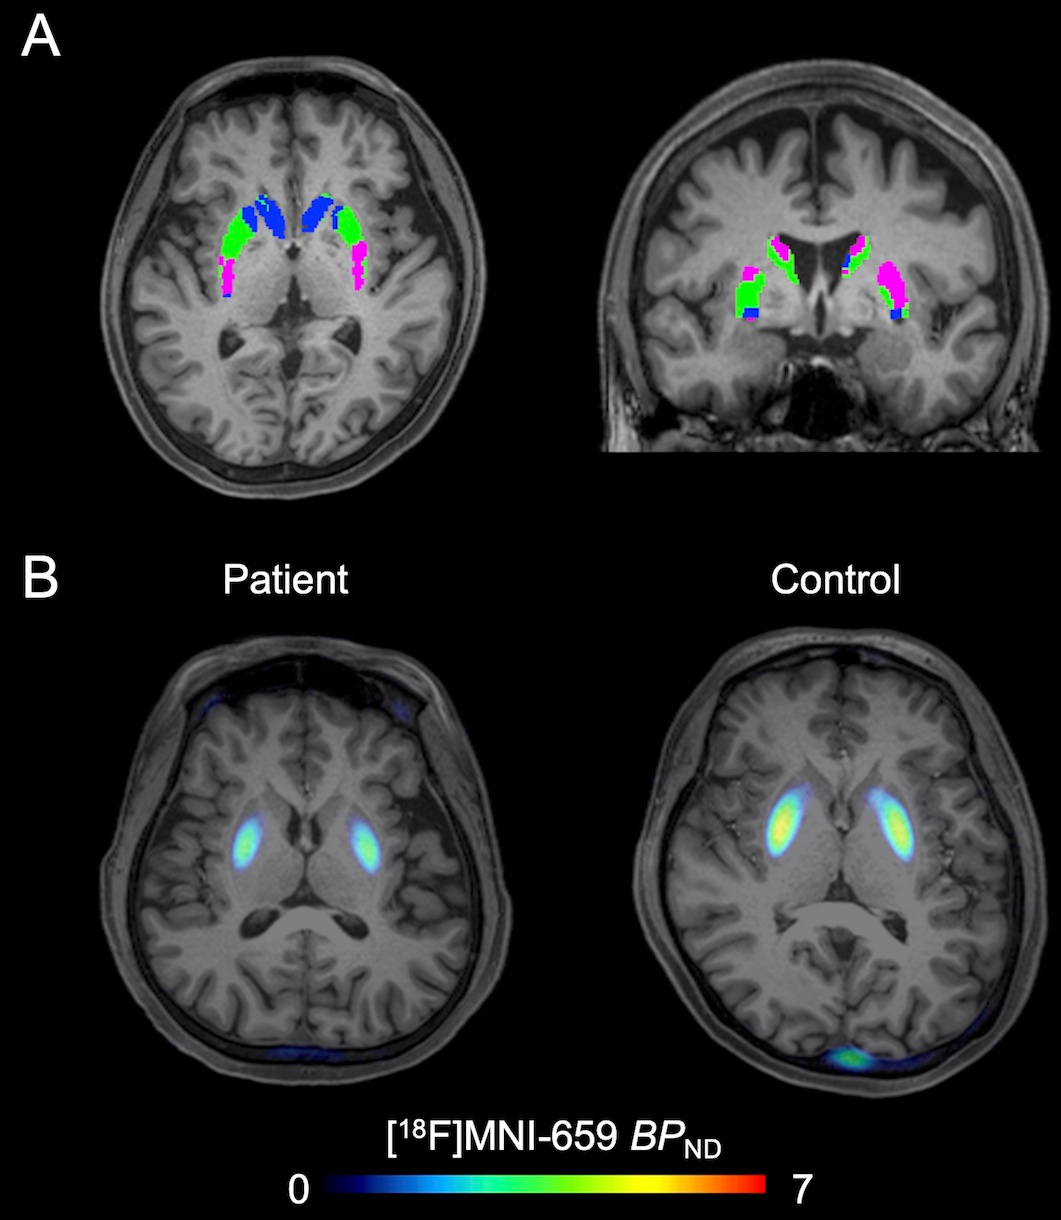

The primary objective of the study was to assess whether striatal PDE10A availability was altered in patients with BD-I compared to healthy controls and to examine the relationship between these alterations and the clinical characteristics of BD-I. This was achieved using positron emission tomography (PET) scans with a radioligand that binds to PDE10A, providing a detailed view of its availability in different regions of the brain.

We focused on the striatum, a brain region known for its involvement in regulating mood, cognition, and motor control. The study included 25 patients diagnosed with BD-I and 27 age- and sex-matched healthy controls. Importantly, most of the BD-I patients were in a euthymic state, meaning they were not currently experiencing manic or depressive episodes, allowing the researchers to focus on trait-related changes rather than state-dependent effects.

The key finding was that patients with BD-I had significantly lower PDE10A availability in two subregions of the striatum: the executive and sensorimotor areas. The executive subregion, in particular, showed a strong correlation between reduced PDE10A levels and a higher number of mood episodes in the past year. This suggests that diminished PDE10A activity in this area could be linked to a greater risk of recurrent mood episodes, making it a critical area of focus for future research.